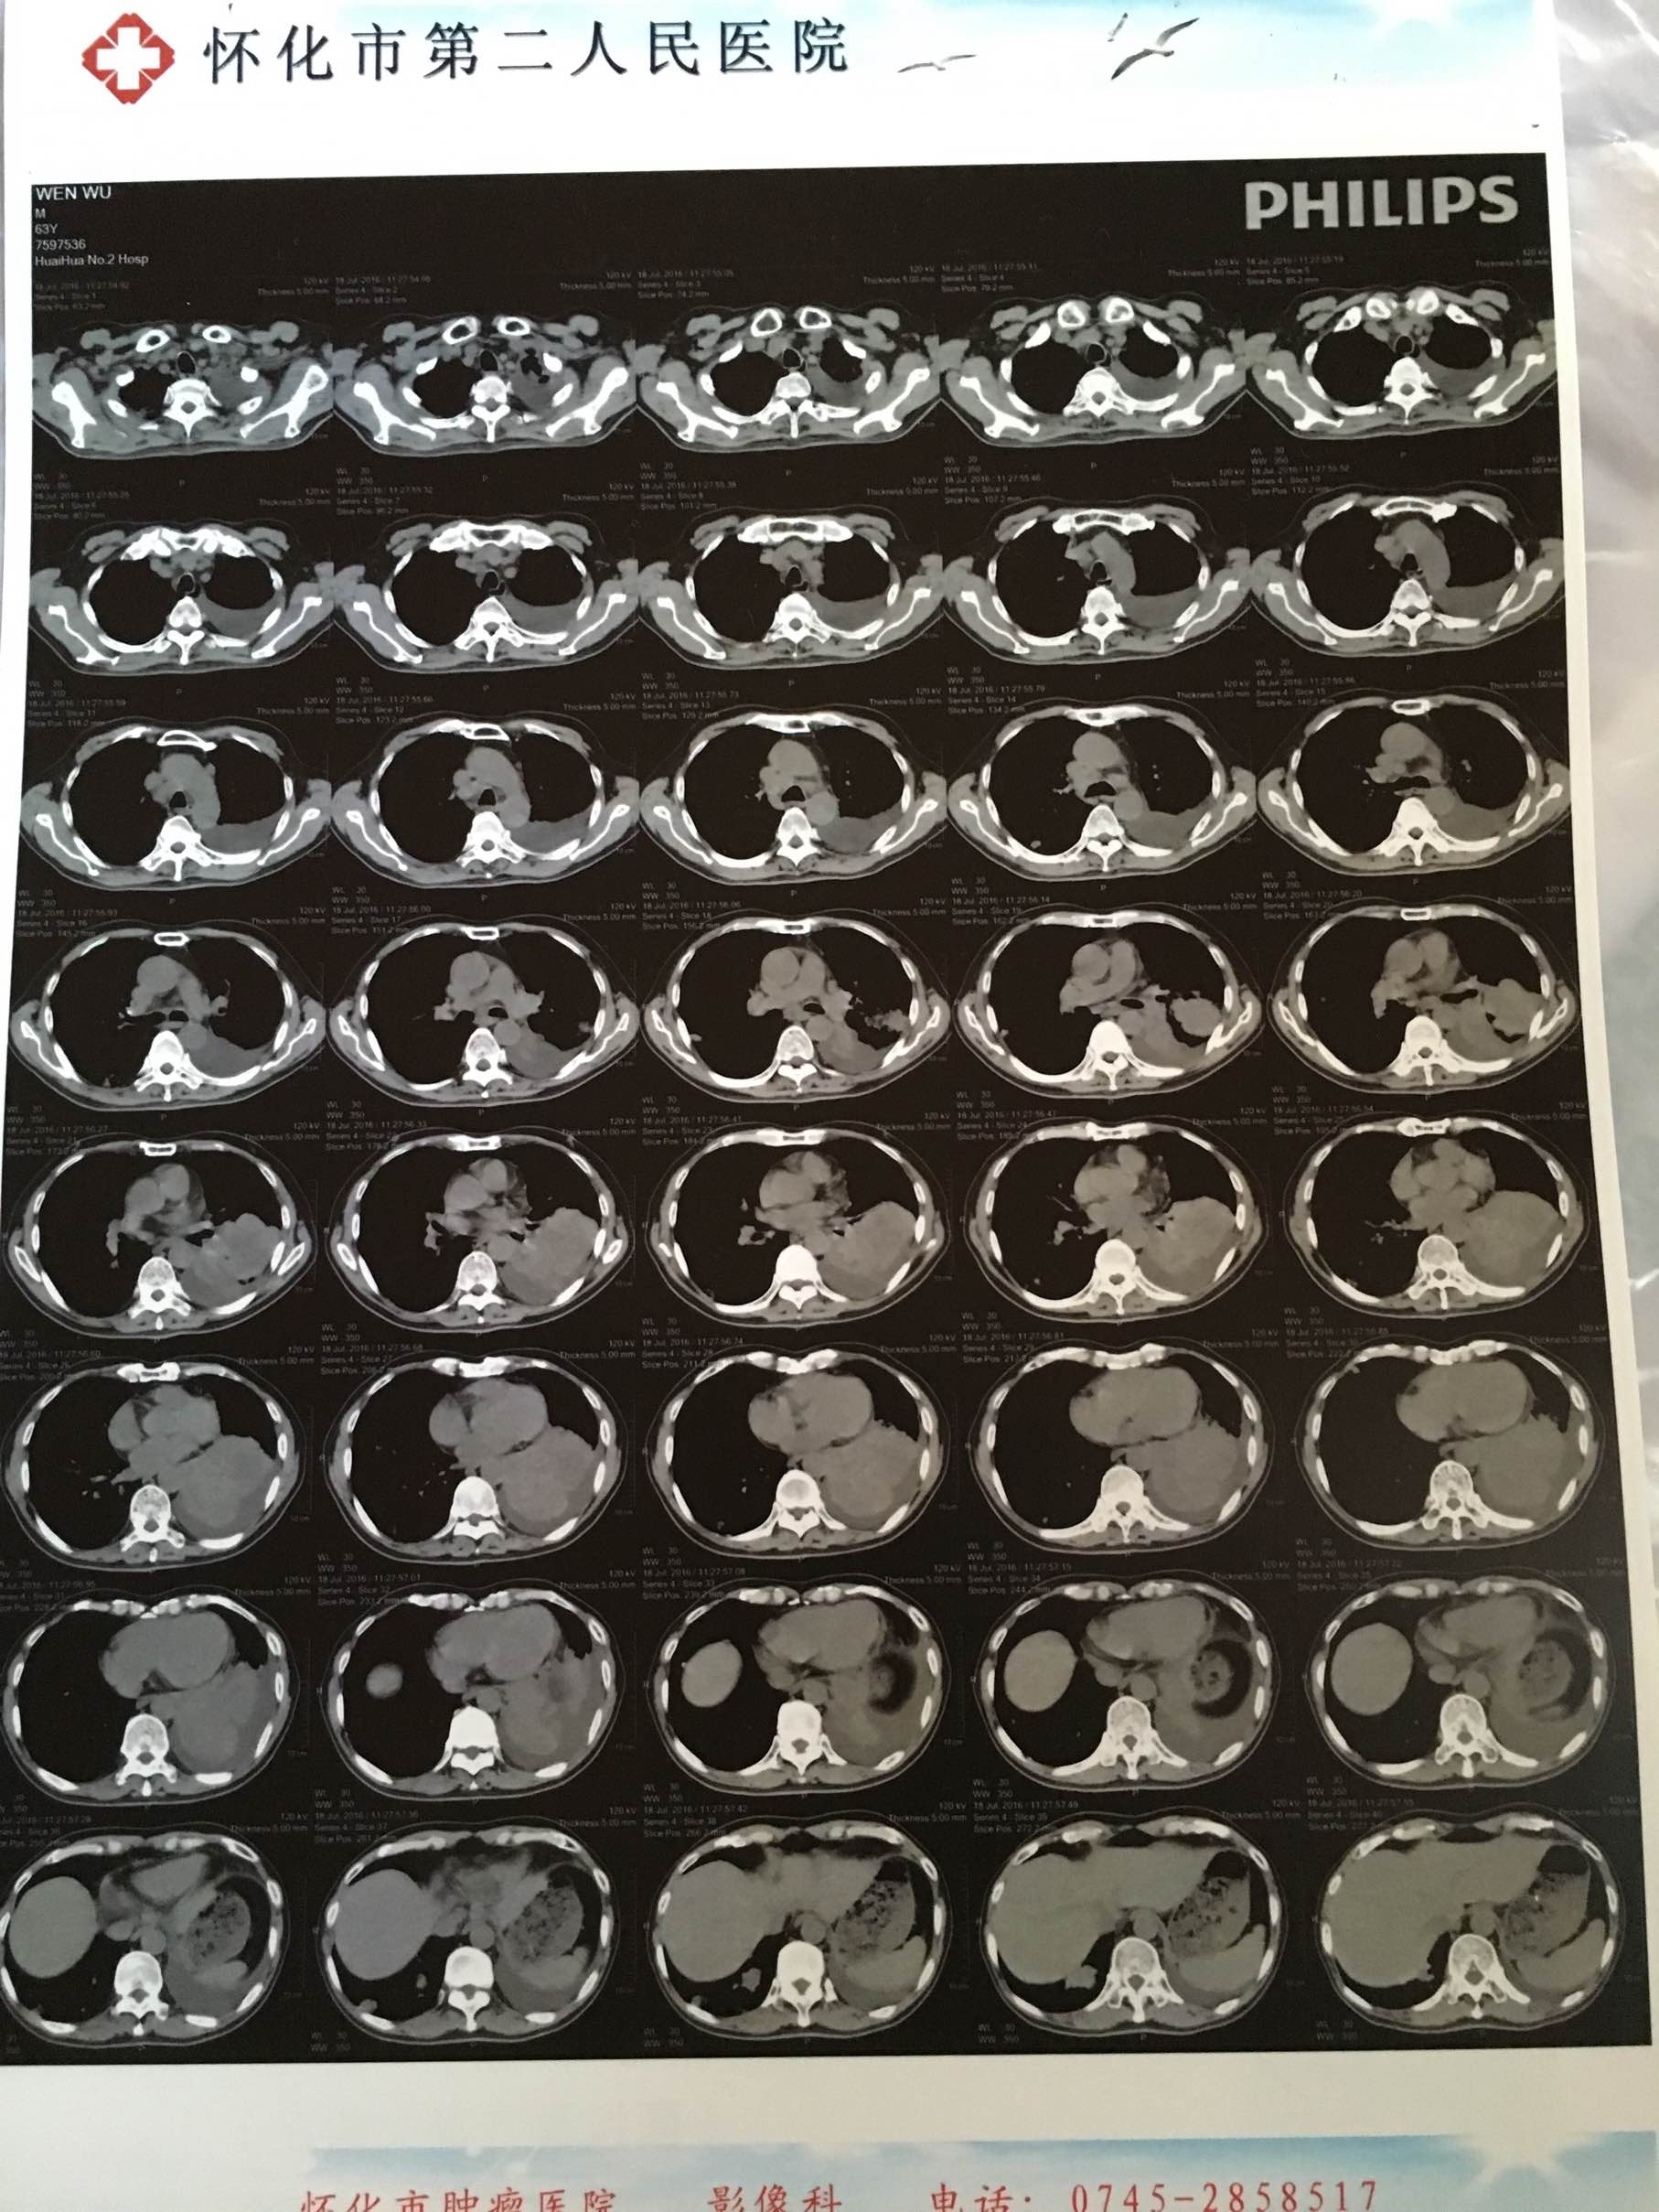

7月18入院检查,CT显示肿瘤明显增大,脑核磁未发现脑转。医生还是建议换药化疗。爸爸不想化疗,他原本寄希望于靶向药,这次试药不成功,心态发生很大改变,以前一直很乐观,现在放弃治疗,总说治不好没必要再花钱。爸爸身体现在太瘦弱又中度贫血而且吃不下饭,我觉得即使化疗也需要调好身体再做。

爸爸确诊肺癌时我刚怀孕,一直是弟弟带爸爸化疗,我现在生完孩子在家,查询爸爸病历,收集到几次CT检查情况,肿瘤大小如下:

2015.9.2 5.0x6.0cm

2015.10.20 3.2x4.2cm

2015.11.26 3.2x4.2cm

2016.1.14 4.4x6.4cm

2016.3.29 6.4x8.2cm

2016.5.19 5.4x5.8x5.4cm

2016.7.18 6.7x6.5x7.5cm